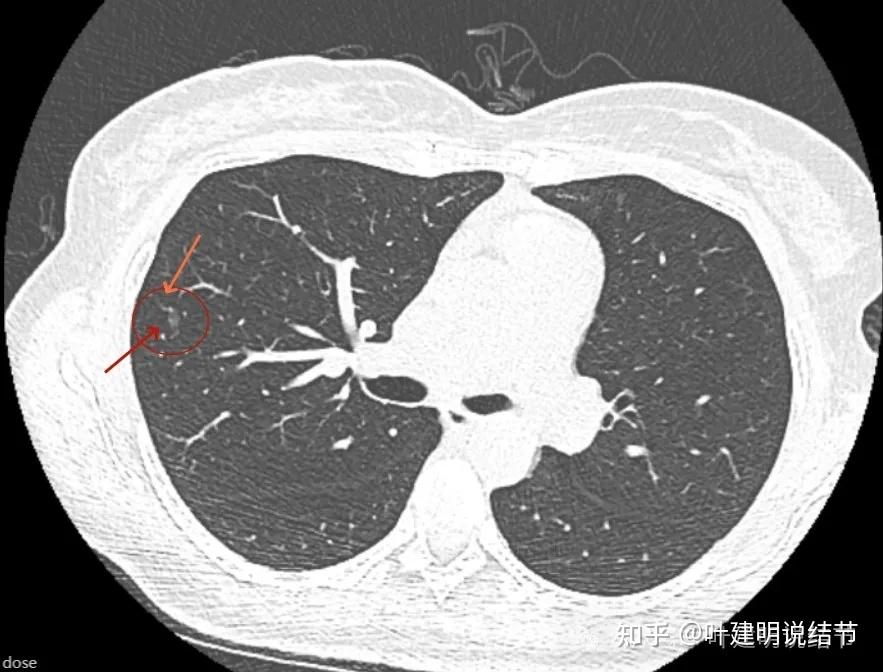

影像展示与分析:

病灶出现,磨玻璃密度,有微小血管似走向病灶,挨得较近。

整体轮廓清,密度稍不均,与周围血管挨的比较近。

瘤肺边界清,有极微细的血管似进入病灶,但肯定没有异常增粗与显著穿行。

瘤肺边界清,整体轮廓清楚。

有微血管进入。

微血管进入以及部分边缘细毛刺征。

部分边缘表面不光滑,略毛糙。

2023年2月份的形态与密度测量值(患者提供的截图,我是从来没有测量具体数值的)

2024年3月手术前的病灶形态与测量CT值。

影像判断:

右上叶磨玻璃密度结节,没有实性成分,灶内密度稍不均,整体略显高,但肯定没到实性密度;整体轮廓清,瘤肺边界清楚,随访持续存在,符合磨玻璃为表现的早期肺癌影像;有微血管进入但无异常增粗或穿行;部分边缘略不平整,有细毛刺征。单从影像特征考虑,此病灶应该与原位癌或微浸润性腺癌比较符合,也不能除外浸润性腺癌的贴壁为主型。但风险不高,切缘阴性应该就是治愈。